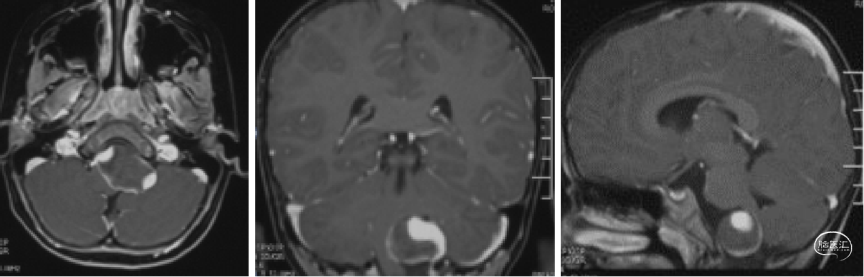

头颅MRI

血栓化动脉瘤瘤体巨大,虽无明显相关症状,但影像显示瘤体对脑干及周围神经组织压迫明显,需行动脉瘤孤立术,减轻瘤体占位效应。

若行动脉瘤孤立术,需重建PICA血流,预防小脑及延髓外侧梗塞;而幼儿后循环搭桥手术难度极大。

显露动脉瘤远端椎动脉困难(中线对侧延髓前方),而经岩骨幕上下入路可能有助于显露,但创伤极大,幼儿难以耐受。